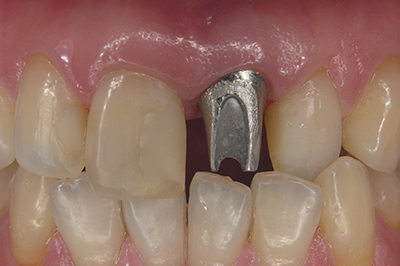

治療例2

歯ぐきが安定した状態

土台をたてた

噛める機能を回復